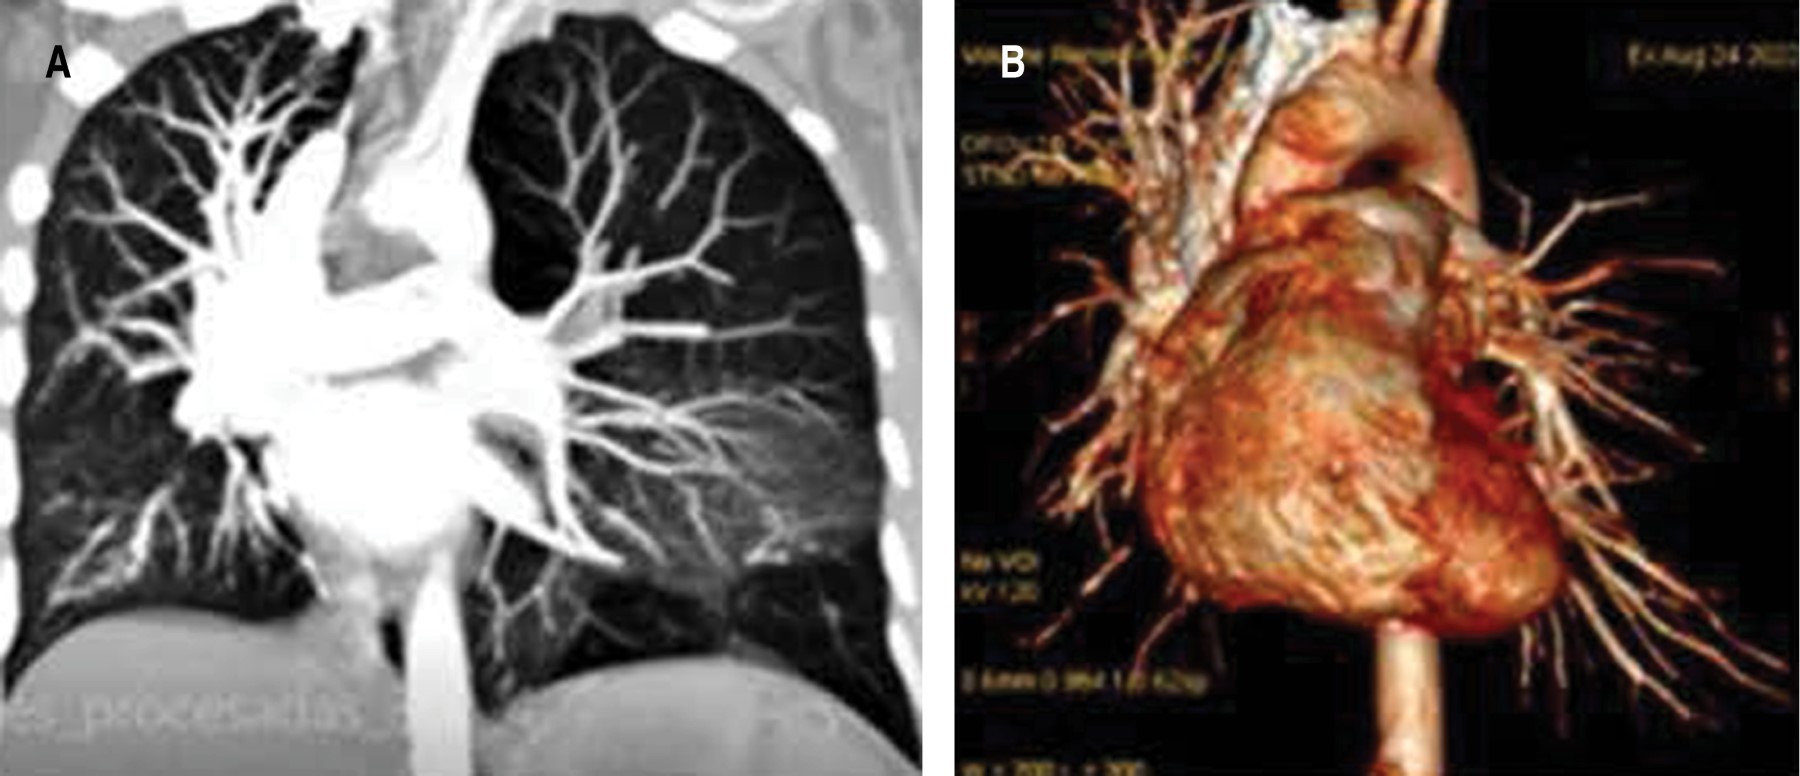

Ruling out probable pulmonary thromboembolism (PTE), CT angiography was requested, which showed no evidence of PTE in the digital reconstructions, showing continuity of opacification of first and second order pulmonary arteries. Lung with left hyperclarity and hypoplasia of the ipsilateral pulmonary artery measuring 9 mm in diameter A-P compared to 20 mm on the right. Consider Swyer James MacLeod syndrome (Figure 2). Echocardiogram, reports dextrocardia with EF at 55%. Low probability of PAH with pulmonary systolic pressure at 20 mmHg. Abdominal CT reports no abnormalities.

A mild chest pain prompted consultation and radiography showed a hyperlucent left lung. It is most commonly diagnosed in infancy, typically occurring in children under eight years of age, before the lung has completed lung development and maturation.5 It may run asymptomatically into adulthood, present with usually asymptomatic spontaneous pneumothorax,2 or as a rare emergency condition,3 as calcified bullae6 and with placental transfiguration of the lung parenchyma.7 The patient's chest X-ray and CT scan showed hyperlucent segmental lung with altered vascularity, which is usually described by other authors as unilateral or lobar pulmonary hyperclarity, associated with air trapping of the hyperlucent lung during expiration.2,5,8 In order to rule out the differential diagnosis of pulmonary thromboembolism, angiotomography was requested, which showed anatomical abnormalities of the left pulmonary artery with a smaller caliber and decreased flow. The spirometric pattern showed restrictive process. Pulmonary scintigraphy was not performed that could show decreased ventilation of the pathologic lung secondary to emphysematous changes and a marked decrease in perfusion, as a consequence of the reduced caliber of the pulmonary artery.5,8 Therefore, diagnostic criteria for this syndrome require one of the following findings: a) unilateral loss of lung volume with hyperlucency demonstrated by chest radiography; b) unilateral reduction of vascularity on chest CT scan; and c) unilateral loss of perfusion on technetium-99m lung scan.1,2